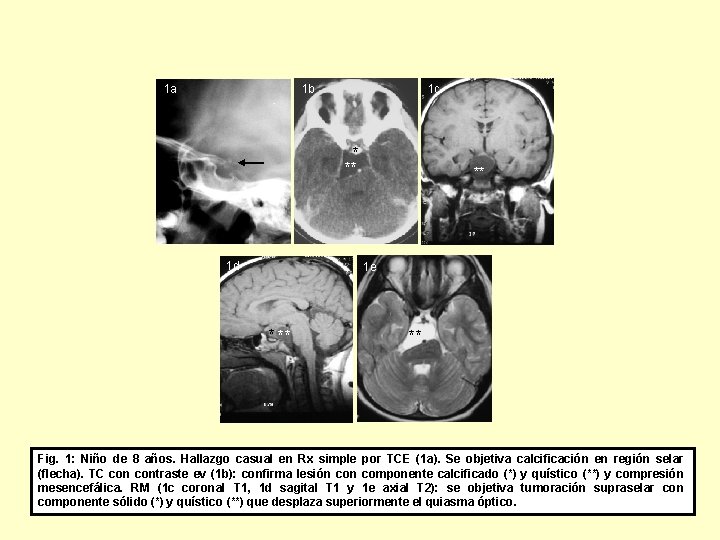

1 a 1 b 1 c * ** 1 d ** 1 e * ** ** Fig. 1: Niño de 8 años. Hallazgo casual en Rx simple por TCE (1 a). Se objetiva calcificación en región selar (flecha). TC contraste ev (1 b): confirma lesión componente calcificado (*) y quístico (**) y compresión mesencefálica. RM (1 c coronal T 1, 1 d sagital T 1 y 1 e axial T 2): se objetiva tumoración supraselar con componente sólido (*) y quístico (**) que desplaza superiormente el quiasma óptico.